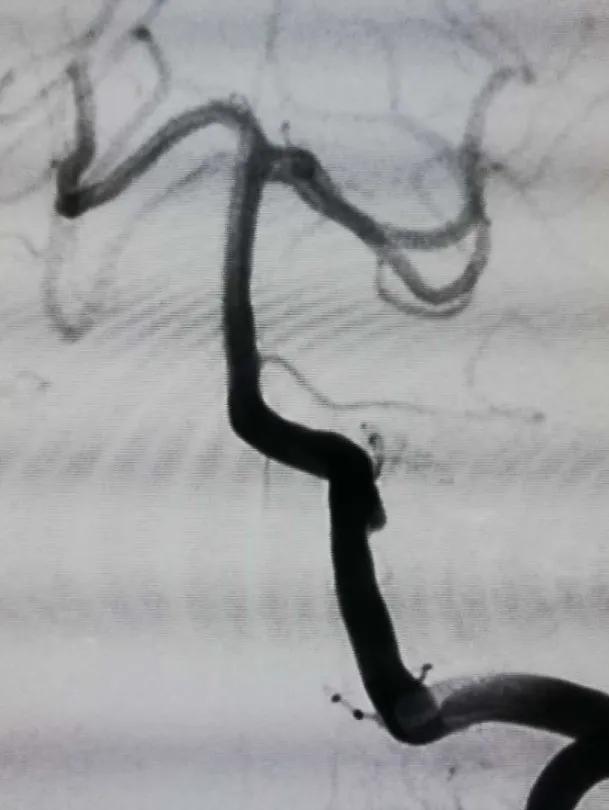

连接高压肝素盐水冲洗装置,6F导引导管在超滑导丝引导下超选进入左椎动脉入路段,行左椎动脉3D旋转造影并选取工作位,见左椎动脉V4段夹层动脉瘤,瘤颈约0.9cm,载瘤动脉约3.7mm(见下图)。

术中诊断:左侧椎动脉V4段夹层动脉瘤。